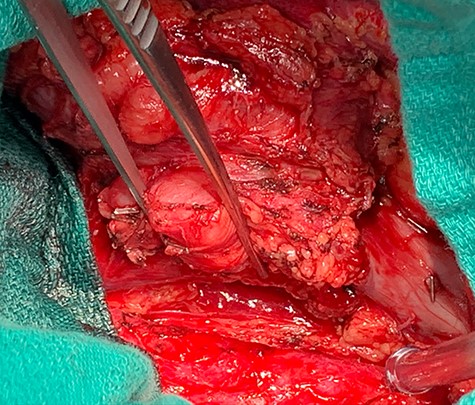

Dissection of primary tumor away abdominal aorta pictured in the lower aspect of the image.

A midline exploratory laparotomy was performed. The tumor extended from inferior to the renal veins to superiorly of the bifurcation. The tumor abutted and partially encased the aorta but did not invade it. Once the tumor was fully mobilized, the patient was heparinized and the vena cava was proximally and distally clamped (Fig 5). The vena cava and tumor were removed en bloc and sent to histopathology. A 22 mm Gelweave Dacron graft was inserted using 5–0 Prolene both proximally and distally (Fig 6). Clamps were removed, and hemostasis was achieved with an overall estimated blood loss of 50 ml. Histopathology of the specimen confirmed an LMS with clear surgical margins.